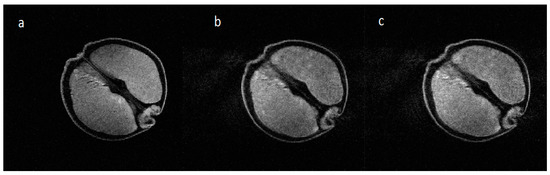

Typical artifacts obtained during neonatal in-plane head rotation, as observed visually during scanning, are shown in Figure 3 [11].

Figure 3. The image on the left is a Fast Spin Echo (FSE) image acquired over two minutes showing no motion artefact, the image in the middle is the same sequence showing artifact due to neonatal in-plane rotational head movement, as noted visually, which is commonly seen when imaging neonates [11]. The image on the right is a single shot fast spin echo showing no motion artefact but with inferior signal to noise ratio and resolution.